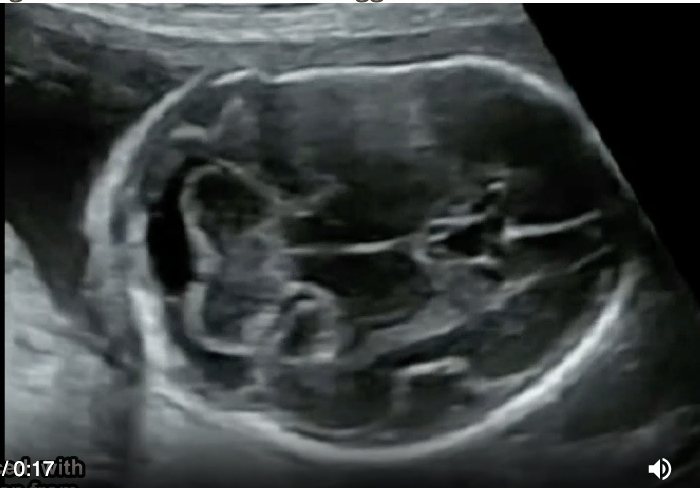

a pt has recent acute onset HTN, nausea, vomit. she has no pain, cramping, or vaginal bleeding. a prior US at 6w indicates the pregnancy should now be 17w6d GA. the image shows strong suspicion of

.

video is of trophoblastic gestation/molar - most fetuses have asymmetrical large head + small body

a) trisomy 21

b) triploidy

c) trisomy 13

d) trisomy 18